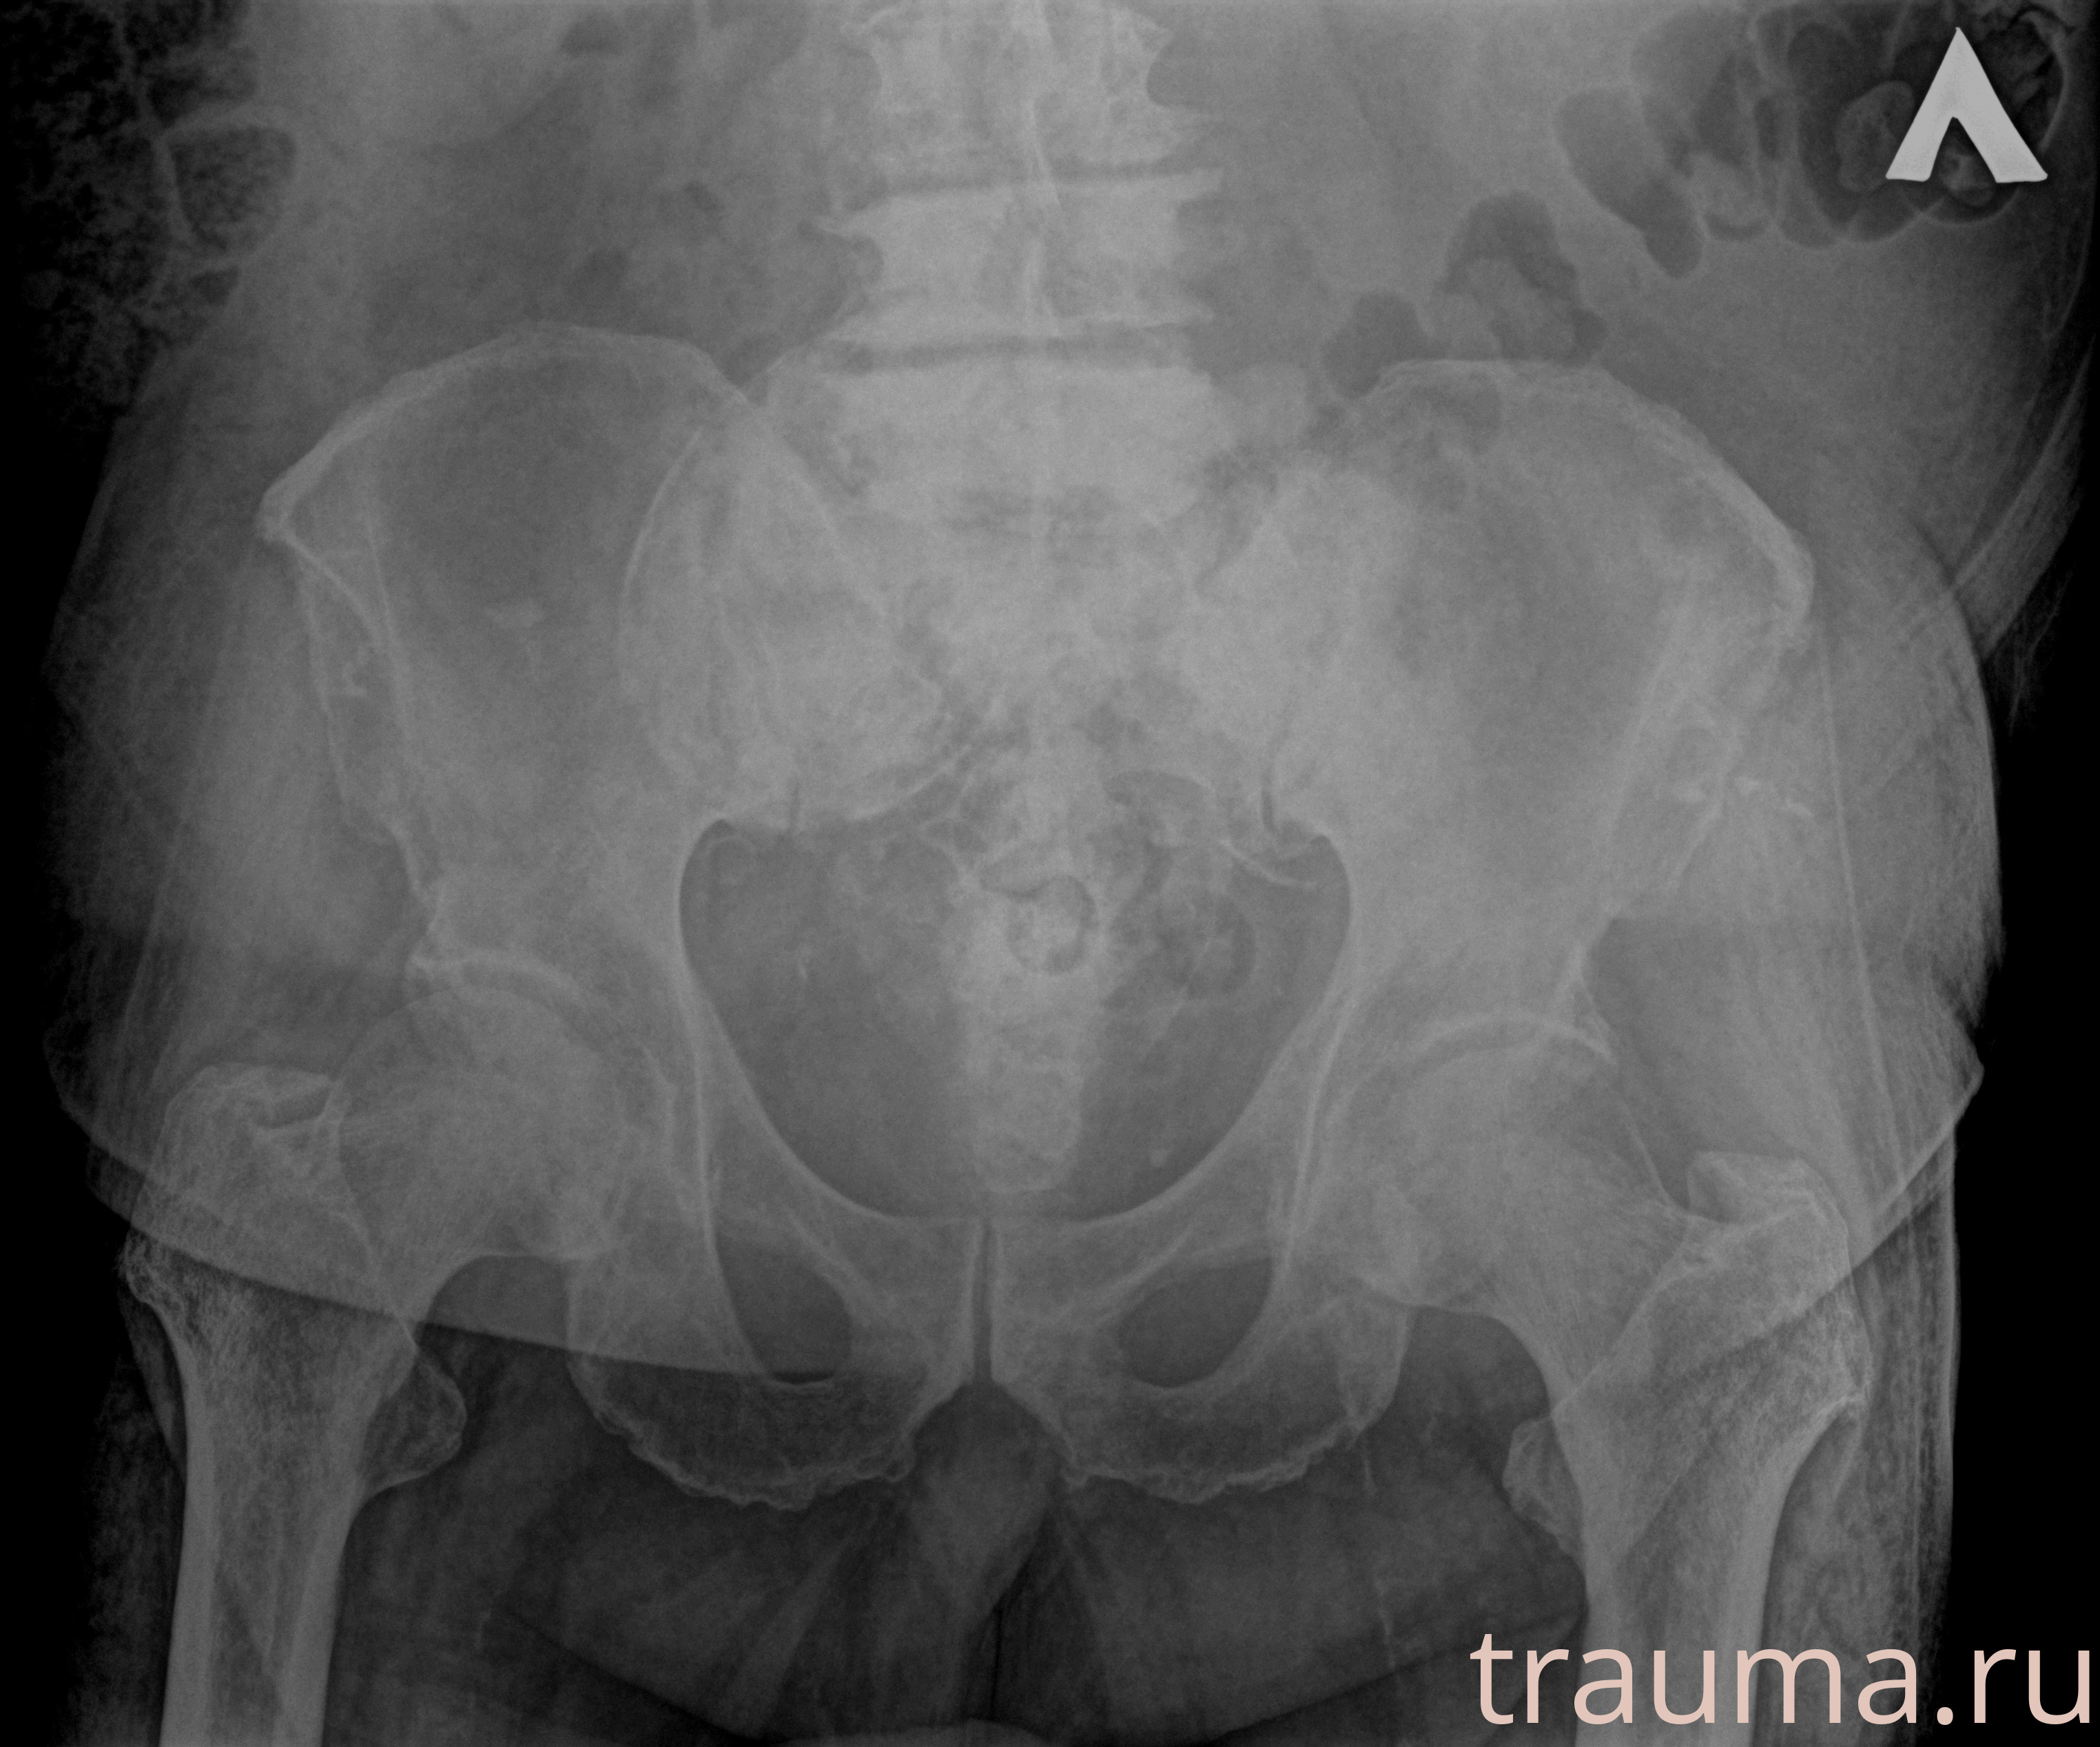

Первая помощь при переломе шейки бедра

Рентген на дому: по вашему адресу приезжает врач-рентгенолог, травматолог-ортопед с мобильным рентгеновским аппаратом, проводит диагностику травмы или заболевания, делает необходимые рентгенограммы, дает рекомендации по дальнейшему лечению. Получить качественные снимки в домашних условиях возможно благодаря уникальной методике, разработанной МосРентген Центром для института  Склифосовского